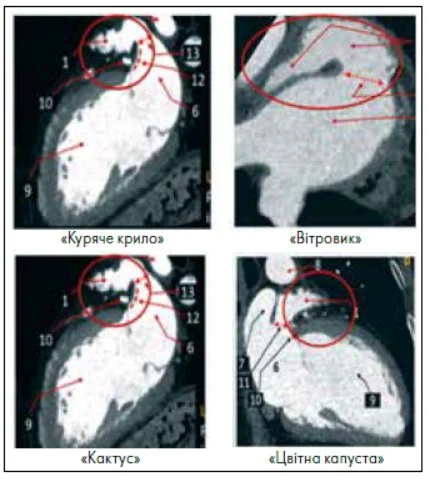

Виділяють чотири основні типові форми ВЛП («куряче крило», «вітровик», «кактус», «цвітна капуста»), які корелюють із різним рівнем застою крові та ризиком тромбоутворення. Варіант «куряче крило» вважається найбільш «безпечним» щодо тромбоутворення та зустрічається у 48‑50% пацієнтів. Особливістю морфологічного типу «кактус», який виявляється у 30% випадків, є вищий ризик тромбоутворення через наявність кількох заглиблень у вигляді кишень. У разі варіанта «вітровик», що характерна для 19‑23% хворих, широка, об’ємна форма сприяє стазу крові, що збільшує ймовірність тромбоутворення. Тип ВЛП «цвітна капуста» відзначається наявністю багатьох відділів та кишеньок і також пов’язаний із підвищеним ризиком тромбоутворення, але зустрічається лише у 5% випадків [2]. Наведені форми ВЛП представлені на рисунку 1. Пацієнти з об’ємними або багатокамерними варіантами потребують ретельнішої стратифікації та, ймовірно, тривалішої АКТ.

Рис. 1. Морфологічна класифікація ВЛП